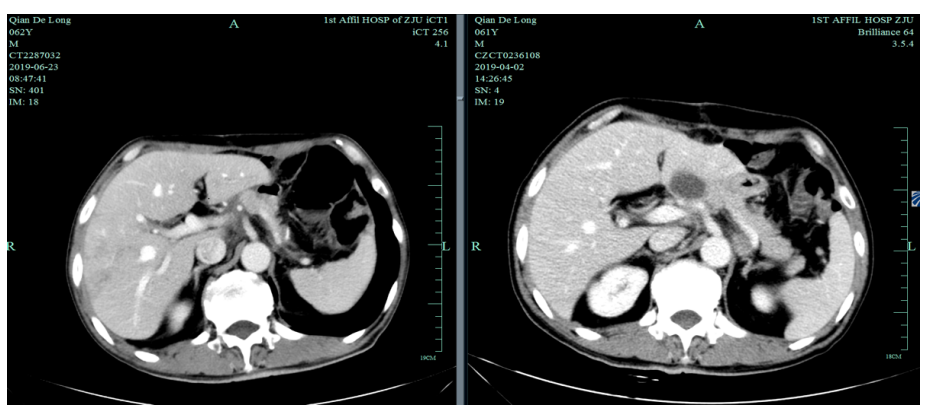

2019-4-2至2019-6-5行SOX+赫赛汀 q3w 4周期联合化疗:具体为奥沙利铂220mgD1、替吉奥3# BID D1-14、赫赛汀400mg(首次)+300mg。

一线化疗疗效评估(2019.6 vs 2019.4):胃癌术后改变。影像评估CR。

2020-11-3全腹部CT平扫+增强提示胃癌术后改变,术周及腹膜后多发肿大淋巴结显示,对照2020-7-7CT淋巴结肿大进展,结合临床疗效评估PD。